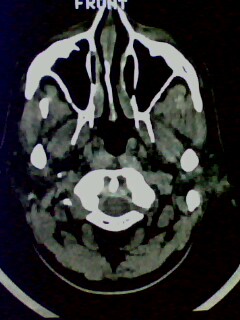

以下是引用随光逐影在2009-5-20 19:22:00的发言:[br]1)考虑左上颌骨近中线区含牙囊肿。2)鼻中隔右突偏曲。3)双侧下鼻甲肥大。